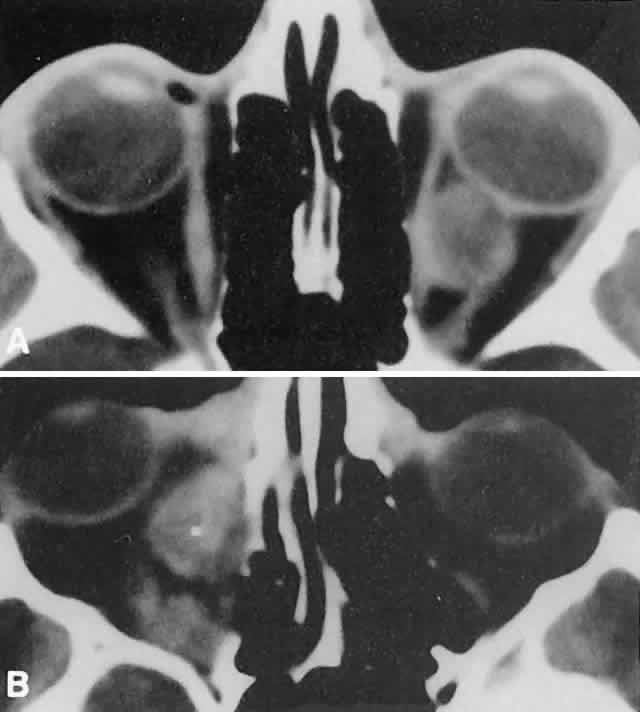

Acute blood cyst formation in this age group makes the distinction between a pre-existent but clinically silent lymphangioma and a rapidly emerging rhabdomyosarcoma a common orbital diagnostic problem. Evidence suggesting an orbitallymphangioma includes the variable finding of conjunctival or eyelid components of the malformation.86 Conjunctival lesions appear as ectatic channels filled with clear or hemorrhagic fluid. Eyelid ecchymosis may result from the seepage of blood out of the thin-walled orbital cysts. Additional developmental anomalies of the eye and adnexa may be present. Other head and neck involvement may be manifest as local hypertrophy (e.g., of the cheek or lips), and cystic palatal lesions may be seen. CT discloses a single or multilobulated mass, which represents only the blood cyst portion of the tumor (Fig. 14). Individual lobules may have different radiodensities depending on the presence of clots or liquefied blood within each cyst (Fig. 15). A generalized increase in orbital dimensions suggests a long-standing, probably congenital process. Echography may help differentiate the cystic components of lymphangioma from cellular rhabdomyosarcoma. Echography shows the blood cysts to be acoustically inactive spaces, with extremely low internal reflectivity (Fig. 16). Clots within the cysts can increase internal heterogeneity, however. MRI has virtually eliminated the need for diagnostic biopsy in this condition, because of its ability to show differing magnetic properties of suspended, degrading blood products (Fig. 17).

The intimate association of orbital lymphangiomas with structures critical to normal vision makes their complete excision almost impossible without incurring vision loss. Because their vascular components do not actively proliferate, the response to radiation therapy is limited and probably is proportionate to whatever lymphoid tissue is present. The presence of a blood cyst is not in itself an indication for treatment if vision is not impaired. In many cases, the blood resorbs during several weeks without residual problems. Frequently, however, vision is compromised by the sudden expansion of multilobulated cysts that surround the optic nerve, and simple observation may result in permanent deficits. Treatment requires evacuation of the offending cysts in a conservative manner consistent with preservation of vision.84 Because the channels of a lymphangioma are hemodynamically isolated from the systemic circulation (“no flow anomalies”),63 their surgical decompression does not produce brisk new bleeding from within them. Rather, the hemorrhagic risk of surgery involves intraoperative and, more often, postoperative, intrinsic bleeding, creating new blood-filled macrocysts.62 Conservative surgery restricts intraorbital manipulation, involves evacuation of offending blood cysts, and avoids disturbance of nonexpanded portions of the lymphangioma. Extensive dissection for cosmetic purposes should be undertaken with the same respect for the fragility of nonexpanded channels. TRAUMATIC ORBITAL HEMATOMA Although the diagnosis of a traumatic orbital hematoma would seem obvious on the basis of history alone, some element of trauma within a few days of the onset of proptosis is such a common historical finding among small children that it may have little differential value. Conversely, a history of culpable trauma may not always be forthcoming, as in cases of child abuse. In penetrating orbital injuries, the entry wounds suggest the diagnosis. Retained foreign bodies should be ruled out. In blunt injuries, other diagnostic clues are helpful. Ecchymosis may be present but also may be a feature of granulocytic sarcoma, neuroblastoma, or lymphangioma with recent bleeding. CT may show an associated fracture. Most orbital hematomas that result from blunt injury occur in the potential subperiosteal space (Fig. 18). The lack of adjacent sinus opacification and the absence of systemic toxicity differentiate this entity from a subperiosteal abscess, which can have a similar appearance.59 Echography shows the low acoustic reflectivity characteristic of fluid-filled spaces. If a traumatic orbital hematoma has compromised vision by acutely elevating orbital pressure, the pressure should be reduced promptly with a lateral canthotomy and cantholysis. If, conversely, vision is compromised because of extreme globe displacement and optic nerve attenuation, the hematoma should be evacuated.87 This is a relatively simple procedure if the blood is compartmentalized in the subperiosteal space. We favor a lid crease incision, with dissection between orbicularis muscle and orbital septum to the orbital rim. The subperiosteal space is then entered, and the hematoma is evacuated. If vision is not compromised, patients can be treated conservatively. Spontaneous absorption generally follows, but hematomas occasionally enlarge with osmotic imbibition. DERMOID CYST Dermoid and epidermoid cysts often occur in the orbit and paraorbital region. Epidermoid cysts are lined by stratified squamous epithelium and are filled with desquamated keratin. The walls of dermoid cysts include dermal appendages that contribute sebum, sweat, and hair shafts to the cyst contents. Both forms probably result from abnormal invagination of surface ectoderm during fetal development. Differences may relate to the depth of tissue that has been sequestered or to the degree of ectodermal differentiation at the time of inclusion.88 Most dermoid cysts are closely related to bone suture lines, suggesting that the surface ectoderm has been trapped between fusing mesodermal processes. Dermoid cysts are most often encountered at the frontozygomatic articulation but can occur at other suture lines, including those deep in the orbit. Most lesions are anterior and paraorbital (Fig. 19), located between the orbicularis muscle and the periosteum overlying the orbital rim, and have a fibrous stalk to the suture line. Anterior cysts produce minimal bone change. Other lesions may be entirely intraorbital, causing proptosis and globe displacement. Their expansion produces an overall increase in orbital volume as well as local bone changes (Fig. 20). Dermoid and epidermoid cysts also may be largely intradiploic, with expansion into the anterior cranial fossa, the temporal fossa, or the orbit. Dumbbell lesions may be present with narrow intraosseous components. Anterior, paraorbital dermoid cysts usually are evident soon after birth. Deeper lesions may not declare themselves until mid- or late childhood, or even the adult years. Expansion of the cysts generally is slow and linear, reflecting continuous desquamation of keratinizing epithelium. There may be a point at which the pressure within the cyst inhibits further proliferation and sloughing of epithelial cells, accounting for the clinically observed stability of many lesions. Sporadic enlargement may be caused by hormonally influenced sebaceous gland secretion or by rupture of the cyst wall with a granulomatous inflammatory response to the cyst contents (see Figs. 19B-D). Such episodic change in an otherwise gradual growth pattern places intraorbital dermoid cysts into the current differential diagnosis. Anterior lesions generally are diagnosed and removed without difficulty, although their occasional occurrence near the lacrimal excretory system can complicate treatment.89 Surgeons should strive for excision of an intact cyst, because residual epithelial elements can lead to recurrence. CT examination of deeper lesions discloses a cystic mass with some internal heterogeneity caused by the different radiodensities of keratin clumps and oily secretions (see Fig. 20B). Bone changes, from shallow fossas to spherical defects, are smooth, with a sclerotic margin and a punched-out appearance. Based on the CT findings, the differential diagnosis includes cholesterol granuloma and unifocal eosinophilic granuloma. Superomedial orbital dermoid cysts must be distinguished from meningoencephaloceles before surgical intervention. Most intraorbital cysts can be removed through a lateral or anterior orbitotomy. The walls of deep lesions may be intimately attached to adjacent bone and may not peel off intact. Gentle use of a high-speed steel burr can facilitate complete removal of the cyst lining. ANEURYSMAL BONE CYST Aneurysmal bone cyst is an uncommon, benign tumor-like lesion of unknown origin.90 Most lesions present in the second decade with pain and swelling. Any bone may be involved, but the long bones and vertebrae are most often affected. Aneurysmal bone cyst of the orbital roof is an unusual cause of rapidly progressive proptosis.91 In one case, a 16-month-old boy was affected.92 The lesions both erode and expand cancellous and cortical bone.90 They are surrounded by a shell of periosteal new bone that prevents their extension into soft tissue. MRI may show fluid-fluid levels indicative of hemorrhage.92 In some cases, aneurysmal bone cyst appears to be a pathophysiologic change superimposed on a pre-existing lesion, such as a giant-cell tumor.90 In most cases, however, the bone cyst is considered a distinct pathologic and radiologic entity. Treatment of facial lesions with intralesional resection or curettage has a substantial rate of recurrence. Recurrence can be reduced with marginal resection or cryotherapy. INFLAMMATORY PSEUDOTUMOR Idiopathic inflammatory pseudotumor (IIPT) is a general term applied to those orbital inflammations without an identified inciting agent and with a sparsely cellular, mixed inflammatory infiltrate that does not suggest a systemic disease. Despite efforts to replace the pseudotumor designation, the term remains entrenched in the literature.93 However, the spectrum of clinical and pathologic conditions included under the rubric has been narrowed and refined since the term was first applied a century ago. IIPT can occur in the first 2 decades of life as well as in adulthood, and it may affect children as young as 3 years of age.94 There appears to be no sex predilection. The condition can be subdivided topographically into myositis, dacryoadenitis, episcleritis/tenonitis/perineuritis, and a localized mass. However, combined forms are common, and even when the process is centered in one structure, inflammatory changes appear microscopically and in imaging studies to spill into adjacent tissues. Among these variants, orbital myositis and dacryoadenitis are the most common forms of IIPT encountered in children. Local tumefactions may occur anywhere in the orbit. When they involve the crowded orbital apex or superior orbital fissure, they can produce the Tolosa-Hunt syndrome of painful ophthalmoplegia. The typical patient with IIPT has an abrupt onset of pain, proptosis, eyelid edema, chemosis, and conjunctival vascular engorgement.94 The left orbit is affected twice as often as the right, but bilateral orbital involvement, either simultaneous or separated by variable intervals, occurs in almost half of the pediatric cases. Among children with IIPT, there is a higher incidence of iritis than among adults with this disorder. Optic nerve head edema is noted in one-third of cases. Systemic complaints are variable but may include fever, malaise, anorexia, and nausea. Orbital symptoms may follow an upper respiratory tract infection. In pediatric cases, laboratory abnormalities may include peripheral blood eosinophilia and elevations of the erythrocyte sedimentation rate, complement level, and antinuclear antibody titer.95 The absence of a marked leukocytosis with a left shift should help differentiate this condition from bacterial orbital cellulitis. Orbital myositis may represent a greater proportion of cases of IIPT in childhood than in adulthood, and involvement of multiple extraocular muscles may occur more frequently in children than inadults. In orbital myositis, early diplopia and increased discomfort with attempted eye movement are typical symptoms. CT may show enlargement of one or more extraocular muscles in one or both orbits (Figs. 21 and 22). When a single muscle is involved, the specter of a primary or metastatic neoplasm within the muscle may be raised. However, external inflammatory signs, considerable pain and limited motility, and an explosive onset of symptoms within 24 hours all suggest orbital myositis. The uniform enlargement of the muscle, including its tendinous insertion (see Fig. 22), also helps distinguish the process from a neoplasm, which might be expected to produce a more focal, globular expansion. Echography may support the diagnosis of inflammation by showing edema in the episcleral space as a relative sonolucency between the scleral and orbital fat echoes (Fig. 23). Its CT counterpart is an increase in the radiodensity and thickness of the ocular tunica.